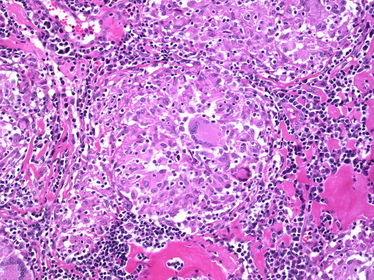

TISSUE TYPE: lymphocyets every where... where am I ??? xD PATHOLOGY: inflamatory granuloma with caseation in the center .. eosinophilic Langhan's cells (an orphan cell in the center) ^^ DIAGNOSIS: tuberculous lymphadenitis KEY: LYMPHOCYTES + CASEATION

TISSUE TYPE: lymphocytes every where ... lumph node PATHOLOGY: granuloma with NO caseation .. langhan's cells (with horse shoe arrangement of nuclei) are seen and epithelioid cells.. DIAGNOSIS: Sarcoidosis N.B: NO caseation in contrary to TB. special charecters : Schaumann and asteroid bodies (Don't even think about seeing them xD).. may be isolated in a question .